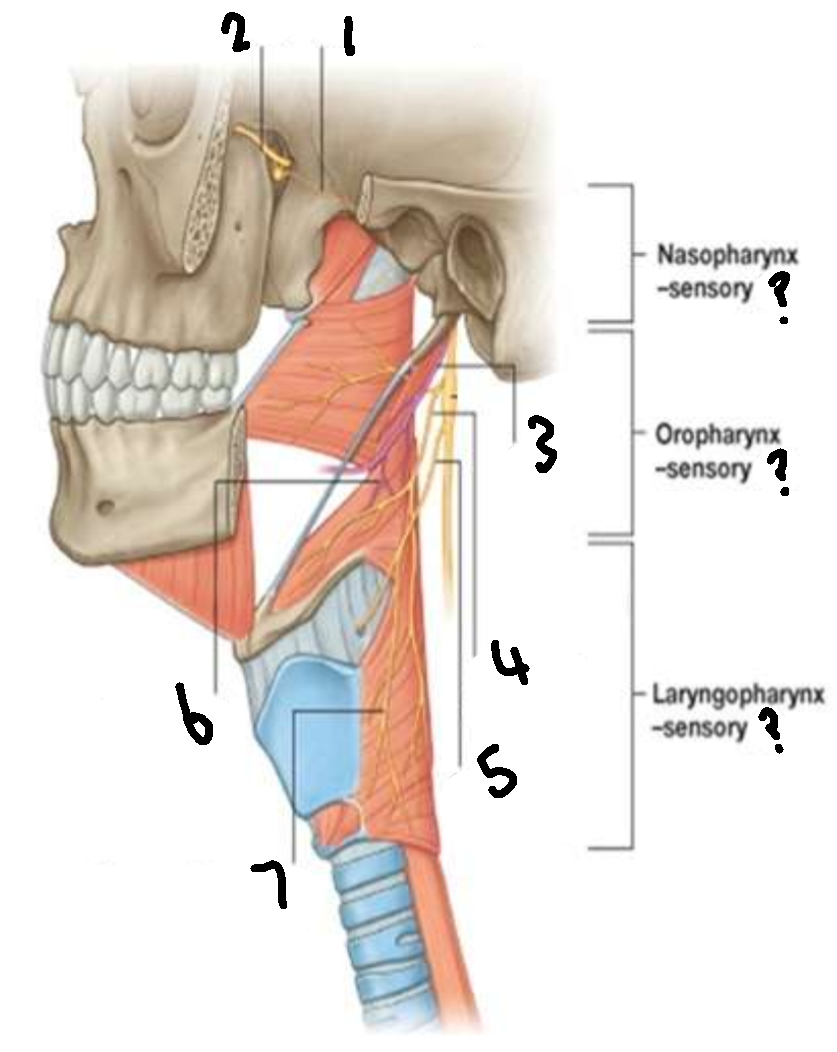

What provides sensory innervation to the nasopharynx?

mandibular branch of trigeminal V2

What provides sensory innervation to the oropharynx?

glossopharyngeal IX

What provides sensory innervation to the laryngopharynx?

vagus X

What is 1?

pharyngeal branch of V2

What is 2?

maxillary branch of trigeminal V2

What is 3?

glossopharyngeal IX

What is 4?

pharyngeal branch of vagus X

What is 5?

superior laryngeal nerve

What is 6?

pharyngeal branch of IX

What is 7?

external laryngeal branch of superior laryngeal nerve of X